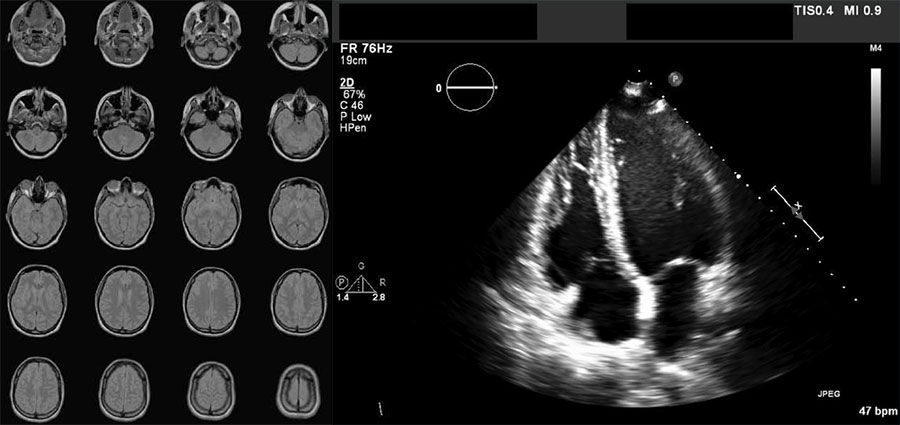

眾所皆知,數據是 AI 的基礎。具備好的資料基礎設施,可降低 AI 訓練的時間和複雜度,這點在醫療業也是一樣的。然而,在醫療領域,數據呈現高度的「異質性」,同時存在結構化的電子病例(EHR、HIS)和非結構化的 DICOM 醫學影像(X 光片、MRI、CT)。

圖一、非結構化 DICOM 影像和結構化電子病歷,傳統系統難以同時兼顧

(圖片來源:https://www.mathworks.com/discovery/dicom.html)